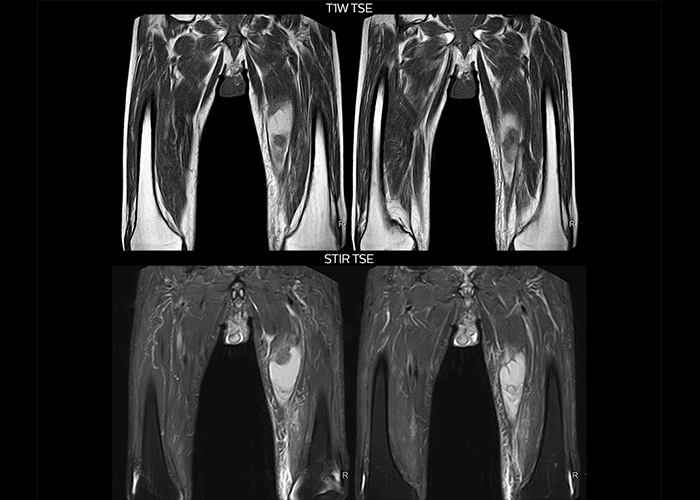

“On average, we scan about 80 patients per day, but on some days we scan well over 100 patients. The scanner is in use 7 days per week, operated 20 hours per day on week days and 8 hours per day in the weekend,” Mr. Tuna says. “To avoid coil changes we plan examinations of similar anatomies back to back, such as head and spine. Multiva helps us here a lot because coils don’t need to be changed frequently. Moreover, thanks to parallel imaging technology and 16-channel HeadSpineTorso and 8-channel MSK coils we are able to achieve excellent image quality. In this way Multiva helped us to increase both image quality and productivity.” “Neurological cases, such as brain and spine imaging, represent the largest share in our MR scanning, followed by musculoskeletal cases. In general, we use simple and basic imaging protocols. But occasionally, we use advanced techniques for problematic cases if necessary.